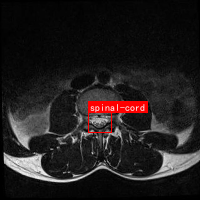

图3展示了SCcConv注意力机制的可视化结果。从图中可以看出,经过SCcConv处理后,模型能够更准确地聚焦于脊髓区域,抑制周围无关组织的干扰。这种注意力引导的特征提取方式是提升检测精度的关键因素。